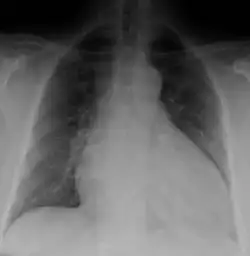

Generalized enlargement of the heart is seen upon normal chest X-ray. Pleural effusion may also be noticed, which is due to pulmonary venous hypertension.[28]